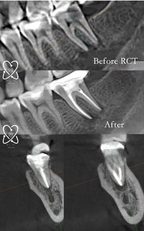

📷 Visual Note:

The imagery used here represents digital 3D models of the treatment process to avoid displaying graphic surgical content.